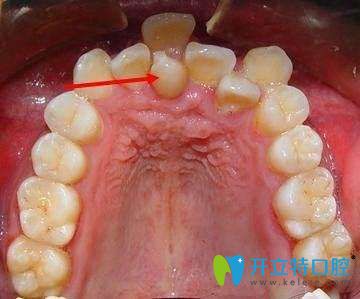

其實(shí)牙齒錯(cuò)位的危害是非常大的,有80%左右的牙齒錯(cuò)位的人就會(huì)出現(xiàn)各種口腔疾病,形成牙結(jié)石等,還會(huì)讓牙齒表面色素沉淀影響美觀。所以牙齒錯(cuò)位不容忽視。下面我們就來(lái)具體介紹下牙齒錯(cuò)位的危害。

2、影響牙周組織健康及口腔衛(wèi)生。牙列不齊會(huì)使口腔菌斑易于附著,牙刷也難以接觸,導(dǎo)致牙齦出血、腫脹、口腔異味等癥狀;久而久之還會(huì)累及牙槽骨,出現(xiàn)牙齒松動(dòng)。